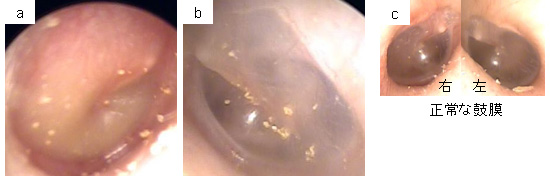

a.右鼓膜、b.左鼓膜、c.正常の鼓膜(左右)

右鼓膜は、赤くなり盛り上がっています。左鼓膜は、ほぼ正常ですが、正常鼓膜に比べると、やや奥側に引っ込んで、くぼんだようになっています。左側の鼓膜の微妙な引っ込みは、鼓膜を見慣れていないと、分かりにくいかもしれません。